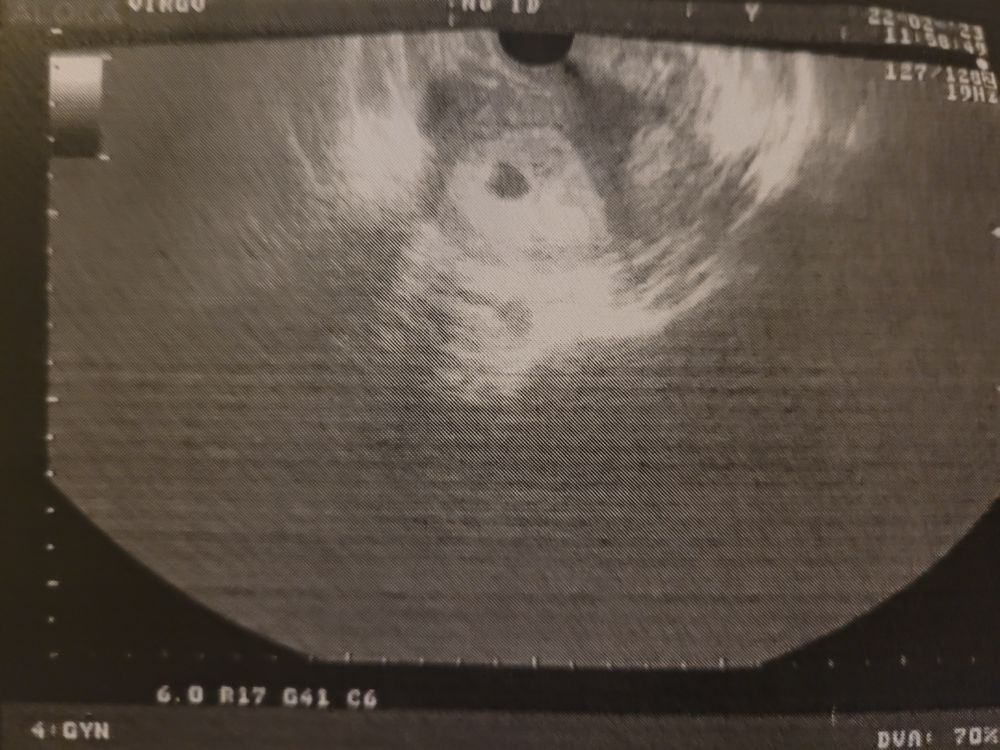

УЗИ, КТГ, доплерИзвините за максимально тупой вопрос , но... кто-нибудь видит желточный мешочек в плодном яйце🤣

Слева.

Извините за максимально тупой вопрос , но... кто-нибудь видит желточный мешочек в плодном яйце🤣